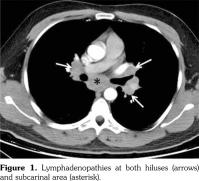

Lymph node biopsy was performed by broncoscopy and endobronchial ultrasonography. Biopsy result was compatible with granulomatous disease. All the infectious studies performed on pulmonary lymph node tissues were negative. Angiotensin converting enzyme level was at the upper limit with a value of 47.6 U/L (normal: 8-52 U/L). Sarcoidosis was found to be compatible with the condition after excluding tuberculosis. Etanercept was ceased following the diagnosis of sarcoidosis. No additional medical treatment was suggested for sarcoidosis. Non- steroid anti-inflammatory drugs were prescribed for the control of AS. Five months later, follow- up thorax computed tomography scan showed resolution of the mediastinal lymphadenopathies (Figure 2).